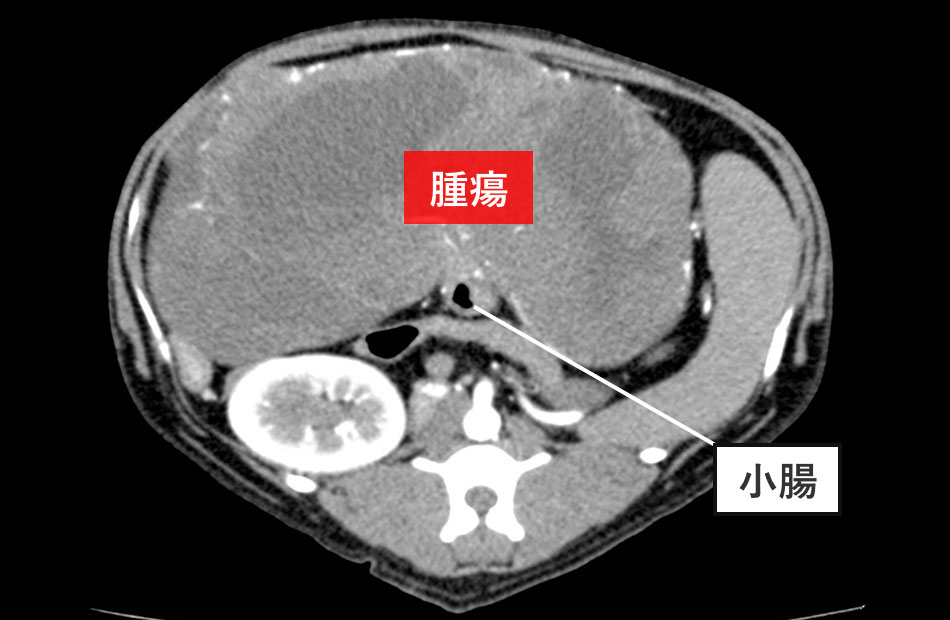

CT検査

腹部の巨大腫瘤は小腸の一部に連続していることを確認しました。また、この巨大腫瘤によって腸間膜動脈を中心とした捻転を生じ(小腸軸捻転症)、一部の腸への血液供給が十分でないことが分かりました。他の臓器に転移を疑う所見は認めませんでした。

検査結果から、「小腸腫瘍」と診断しました。さらに、小腸の外側に向って巨大な腫瘤を形成する特徴から、GIST(消化管間質腫瘍)の可能性が高いと考えました。また、巨大腫瘤によって腸捻転を起こしていることから、早期の手術が必要であると判断し、CT検査を終えて、そのまま手術を行いました。